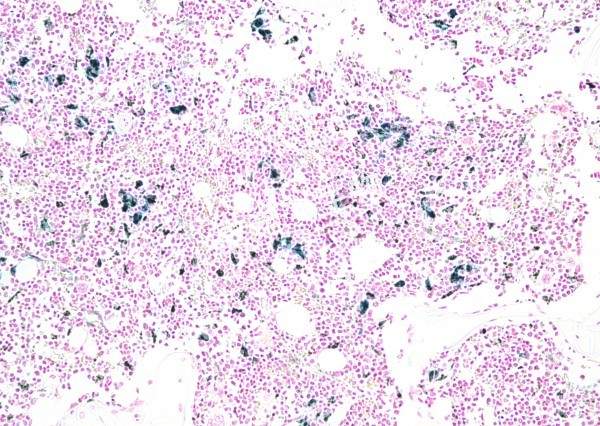

普鲁士蓝 骨髓

特殊特殊-普鲁士蓝-骨髓

下一篇:普鲁士蓝DAB-脾